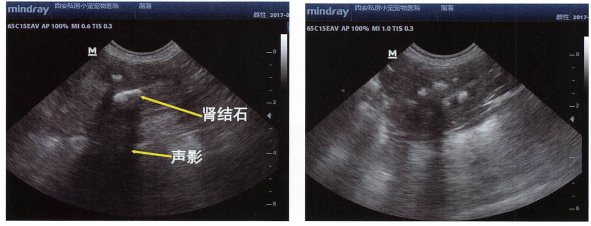

2.何为声影?

骨,钙化灶,结石,纤维化组织,空气声阻抗值都较常见组织差异很大,所以他们的之间的界面就是强烈的声学界面,强烈的声学界面会反射几乎所有的声波,所以声波到达在他们的表面时,几乎全部被反射回探头。而没有声波到达它们的内部,声波无法到达的地方,超声机器不能知道它们内部的结构,这时会出现声影。就像太阳光照到物体上,会有影子一样的道理,超声波也有它到不了的地方,人类形象的把它称为声影。